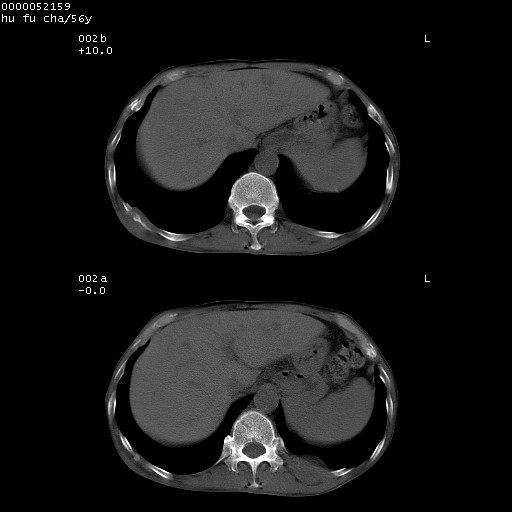

以下是引用zsl6918在2008-8-25 22:47:00的发言:[br]胸骨,胸椎及肋骨均可见多发转移表现,肝内低密度结节不除外转移。原发灶可能在右肺。双侧可见支扩表现。

以下是引用宇宙ct在2008-8-25 23:26:00的发言:[br][br] 胸骨,胸椎及肋骨均可见多发转移表现,肝内低密度结节不除外转移。原发灶可能在右肺。双侧可见支扩表现。 [br] [br]

以下是引用卜一在2008-8-26 8:02:00的发言:[br][br] 支持:肺癌并肺内,胸骨,胁骨,胸椎及肝内转移!另:左肺支气管扩张征伴感染! [br]

以下是引用zjzjr在2008-8-26 11:03:00的发言:[br]支持:肺癌并肺内,胸骨,胁骨,胸椎及肝内转移!另:左肺支气管扩张征伴感染!